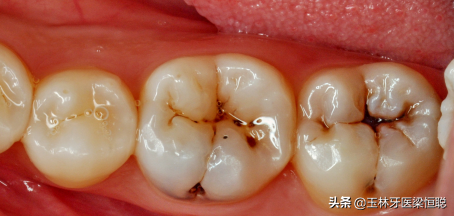

很多患者由于早期沒(méi)有對(duì)蛀牙采取調(diào)節(jié),導(dǎo)致牙齒上有蟲(chóng)洞。牙齒有蛀牙補(bǔ)個(gè)牙齒需要多少錢(qián)?成為一個(gè)熱門(mén)的問(wèn)題。由于很多人都有這樣的困擾,所以這次專(zhuān)門(mén)來(lái)解答牙齒有蛀牙補(bǔ)個(gè)牙齒需要多少錢(qián)?

蛀牙

牙齒有蛀牙補(bǔ)個(gè)牙齒需要多少錢(qián)?牙齒爛個(gè)洞都是由于蛀牙引起的,主要看蛀牙的嚴(yán)重程度決定,以下是一些不同程度的蛀牙。

1、在溫和的情況下,僅在牙釉質(zhì)或牙本質(zhì)層上發(fā)生腐爛時(shí),這是一種常見(jiàn)的牙科填充程序。該程序是指去除所有侵蝕的牙齒腐質(zhì)組織并為復(fù)合樹(shù)脂填充物備洞。先把蛀洞周?chē)哑茐牡慕M織去除,再以適當(dāng)?shù)某涮畈牧线M(jìn)行填補(bǔ),進(jìn)而恢復(fù)牙齒表面的完整性,防止蛀牙的繼續(xù)進(jìn)行。這個(gè)時(shí)候補(bǔ)牙史便宜的。

淺齲初期